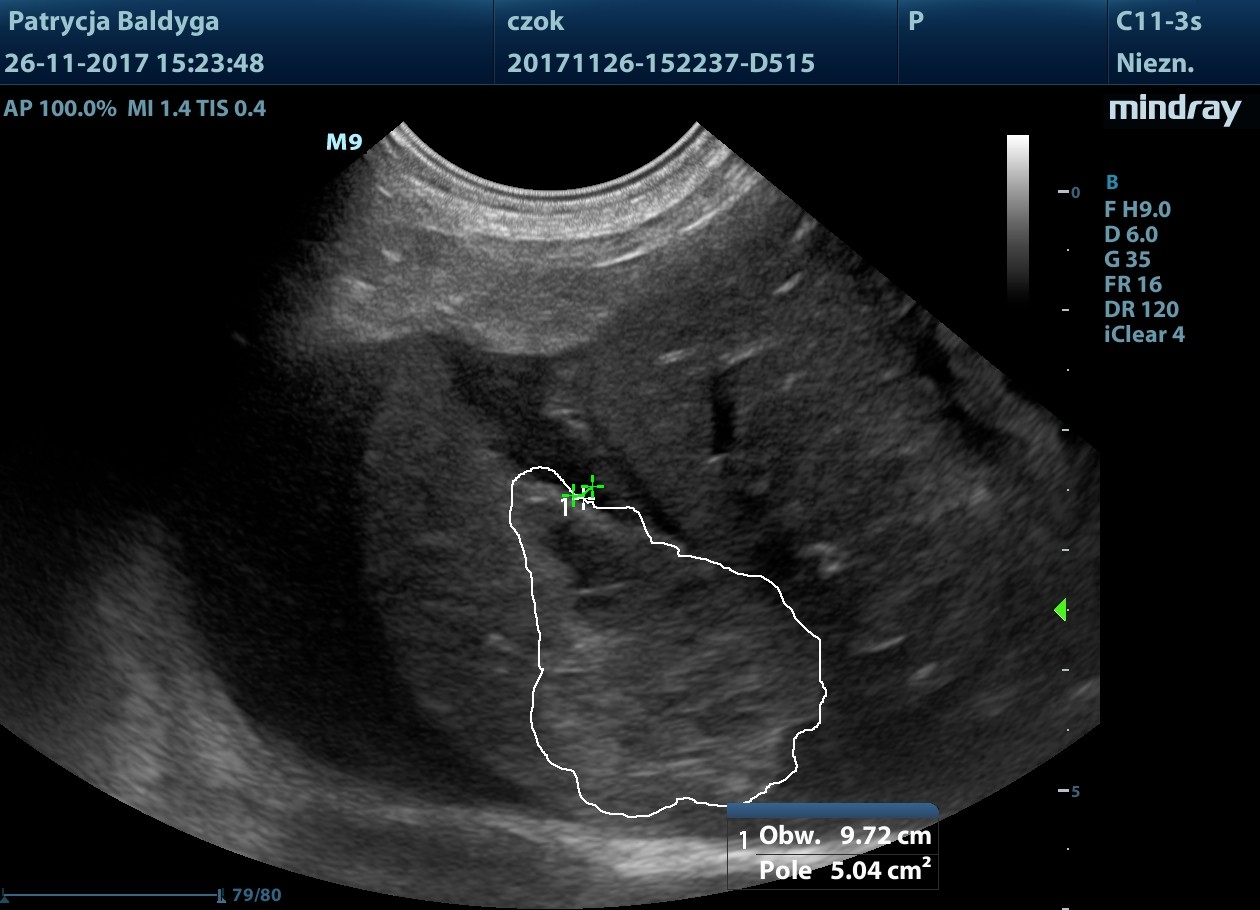

Obecność znacznie zwiększonych ilości wolnego, nieco zagęszczonego płynu w jamie otrzewnej, widocznego w dużej ilości przypęcherzowo, przywątrobowo, pomiędzy pętlami jelit oraz śladowo również w przestrzeni zaotrzewnowej

- co nasuwa duże podejrzenie krwotoku masywnego, najpewniej z wątroby, wskazanie do laparotomii zwiadowczej.